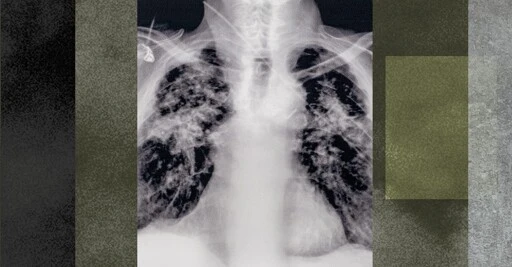

DOGE Is Bringing Back a Deadly Disease